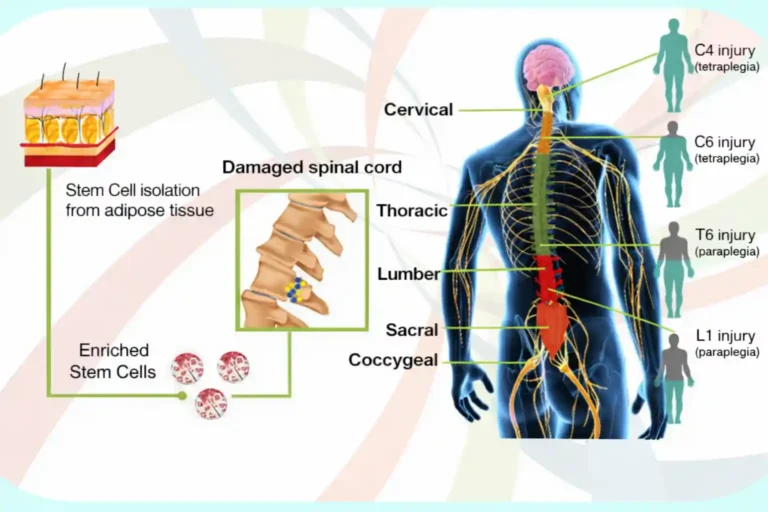

SPINAL CORD INJURY

Definition

Spinal cord injury occurs when trauma or disease damages the spinal cord. This can interrupt communication between the brain and the rest of the body.

Common Symptoms

- Weakness or paralysis below the injury level

- Loss of sensation

- Muscle stiffness or spasms

- Difficulty with bladder or bowel control

- Reduced balance and coordination

How Stem Cell Therapy May Help

Stem cell therapy may support repair of damaged nerve tissue and reduce inflammation around the spinal cord.